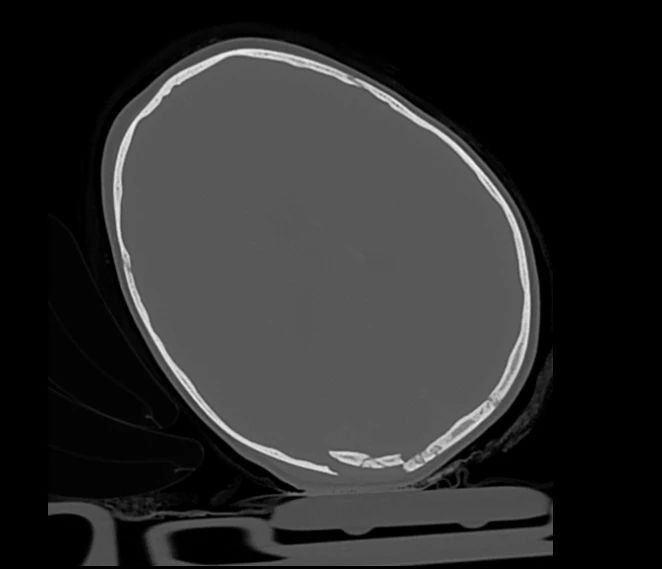

У ребенка – сочетанная травма: черепно-мозговая и перелом бедренной кости. Сейчас он находится в отделении анестезиологии и реанимации. Врачи оказывают всю необходимую помощь, состояние маленького пациента крайне тяжелое.